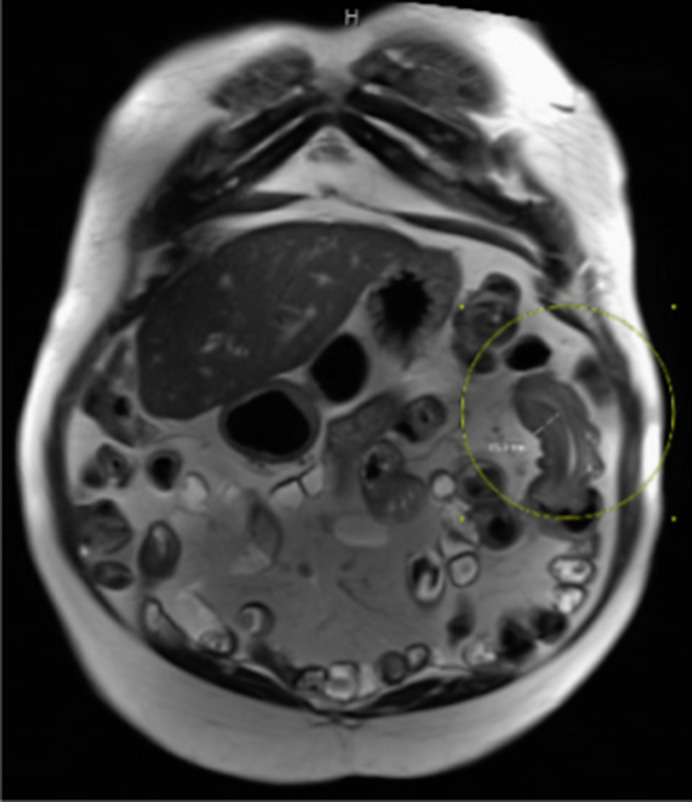

Case presentation: A 70-year-old male with Crohn's disease and chronic anemia presented with recurrent obscure gastrointestinal bleeding. Initial endoscopy was unremarkable, but capsule endoscopy identified a bleeding jejunal lesion. Double-balloon enteroscopy and imaging confirmed a jejunal lipoma causing intermittent intussusception. Due to persistent anemia, the patient underwent laparoscopic resection, with pathology confirming an ulcerated lipoma. His anemia resolved postoperatively.